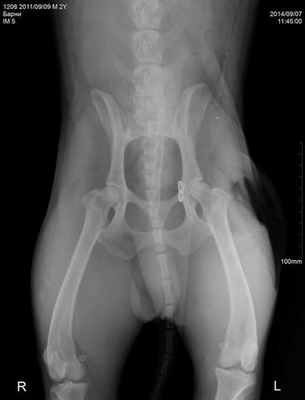

Несмотря на характерные клинические симптомы, для подтверждения диагноза врач обязан сделать рентгеновские снимки в латеральной и вентродорсальной проекциях. Это позволит: подтвердить диагноз, определить направление вывиха, установить отсутствие или присутствие авульсии на месте крепления круглой связки, оценить состояние костей таза, вертлужной впадины, большого вертела бедренной кости и крестцово-подвздошного сустава (Журавков А.А., 2014). Лечение вывиха тазобедренного сустава может быть как консервативным, так и хирургическим. Консервативное лечение вывиха заключается в его закрытой репозиции под седацией и наложением иммобилизирующей повязки. Такой способ лечения допустим при вправимых вывихах, которым не более 2-3 суток. Как правило, по статистике ветеринарной клиники «Самарская Лука», консервативное лечение эффективно не более чем в 25% случаев. В остальных случаях применяется хирургическое его лечение, методов и способов его коррекции в настоящий момент множество.

Травматический вывих тазобедренного сустава у шарпея. Открытое вправление вывиха созданием искусственной круглой связки